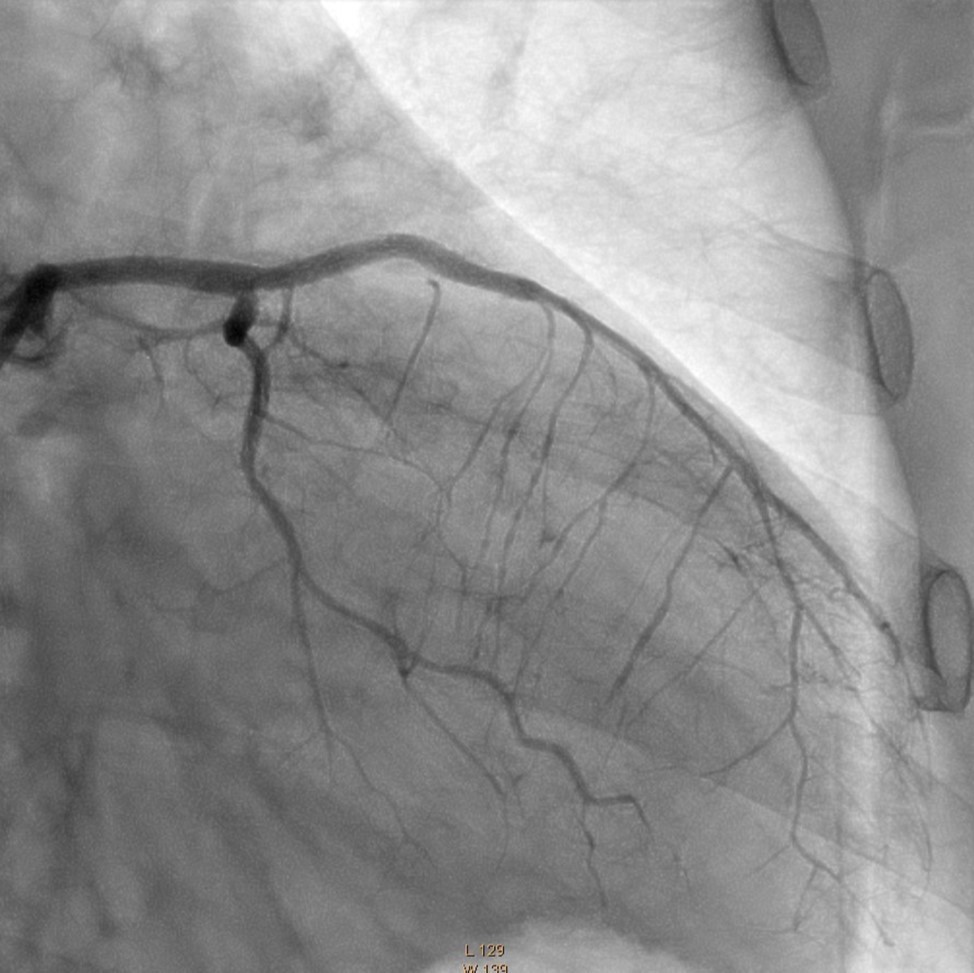

Figure 5.Left Coronary Artery, final result of the intervention.

In the first stage, occluded left main and circumflex arteries were recanalized utilizing the support-balloon technique, and CTO wires (Miracle 3™ wire, Abbott Vascular; Runthrough® NS Intermediate wire, Terumo) and balloon pre dilatation was done (Figure 3). In the second stage, the occluded LAD artery was successfully recanalized by utilizing the support-balloon technique, and CTO wires (Figure 3) (due to severe calcinosis the second stage lasted 40 min). In the third stage, LAD artery, CX artery, as well as LMCA and its bifurcation, were stented with 3 drug-eluting stents (Resolute Integrity Zotarolimus DES, Medtronic), the "Culotte Stenting " technique was used for bifurcation stenting (Figure 4), followed by "Kissing Balloon" post-dilatation technique, and finally, proximal optimization technique was performed in the LMCA. The final angiographic image is good, the intervention ended without complications (Figure 5).